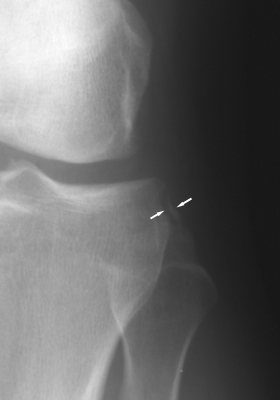

Frontal radiographs of the knee which reveal a small fleck of bone adjacent to the lateral aspect of the lateral tibial plateau. This "lateral capsular sign" is a simple radiographic finding visible on the routine AP knee x-ray, which indicates severe lateral capsular injury and should alert the examiner to the possibility of ACL tear. The fleck of bone represents an avulsion of the meniscotibial portion of the middle one-third of the lateral capsular ligament. It most commonly implies a disruption of the capsular ligament and the ACL. A-B Radiographs. C. MRI confirms the diagnosis of ACL tear.

AP knee - Click on the image for a larger versionAAP knee - Click on the image for a larger versionB - Click on the image for a larger versionC